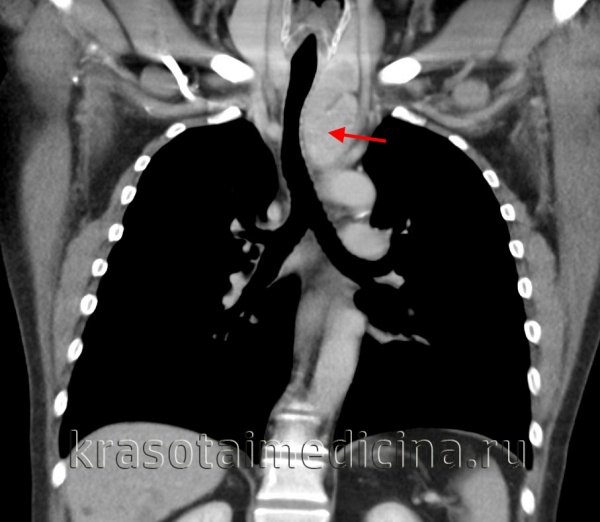

Обязательный перечень рентгенологических исследований включает рентгенографию грудной клетки, рентгенографию пищевода с контрастированием, компьютерную томографию. В большинстве случаев проведенное обследование позволяет установить локализацию рака средостения и распространенность процесса, заинтересованность органов грудной полости (легких, диафрагмы, аорты, грудной стенки). Уточнить состояние мягких тканей в зоне новообразования, выявить метастазы опухоли в лимфоузлы и легкие помогает МРТ.

- Томографическая диагностика. Для более детальной оценки структуры, толщины стенок кисты, характера содержимого и взаимоотношения с соседними анатомическими образованиями, производится КТ и МРТ средостения.